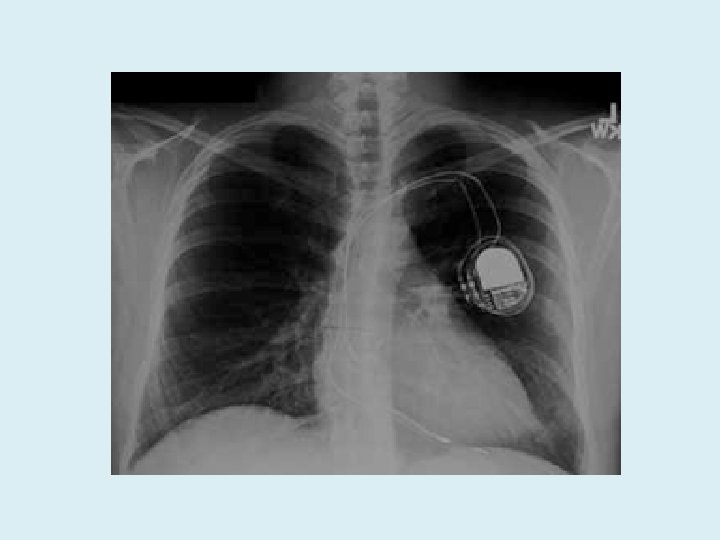

Ambulatory Monitors Holter monitors (spacelabs) • 3 electrodes, usually 24 hrs (48 -72 hr) External event recorders (R test, Novacor) • 2 electrodes, loop recorder, patient activated and also device will record “important” events, 1 -4 weeks Implantable loop recorder (Reveal, Medtronic) • Surgical implant, regular follow ups in CRM clinic, patient activated and also device will record “important” events, 2 -3 yrs